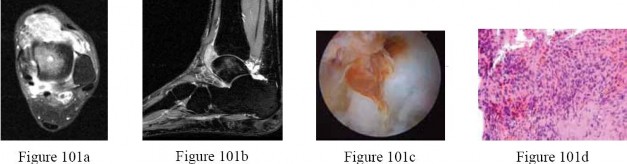

Question 23:

A 55-year-old man presents with chronic, dull, aching shoulder pain. Radiographs reveal an aggressive lytic lesion with 'popcorn' calcifications in the proximal humerus. A core needle biopsy is obtained and the histology slide is shown below. Assuming the biopsy demonstrates hypercellular atypical chondrocytes in a myxoid stroma consistent with a Grade II Chondrosarcoma, what is the most appropriate management strategy?

Correct Answer: Wide surgical resection alone

Explanation:

Chondrosarcomas are generally characterized as chemoresistant and radioresistant tumors. Therefore, the mainstay of treatment for intermediate- (Grade II) and high-grade (Grade III) conventional chondrosarcomas is wide surgical resection alone to achieve negative margins. Intralesional curettage with local adjuvants (like phenol or cryotherapy) is reserved for low-grade (Grade I) or atypical cartilaginous tumors in the appendicular skeleton. Neoadjuvant chemotherapy and radiation play no primary role in conventional chondrosarcoma.